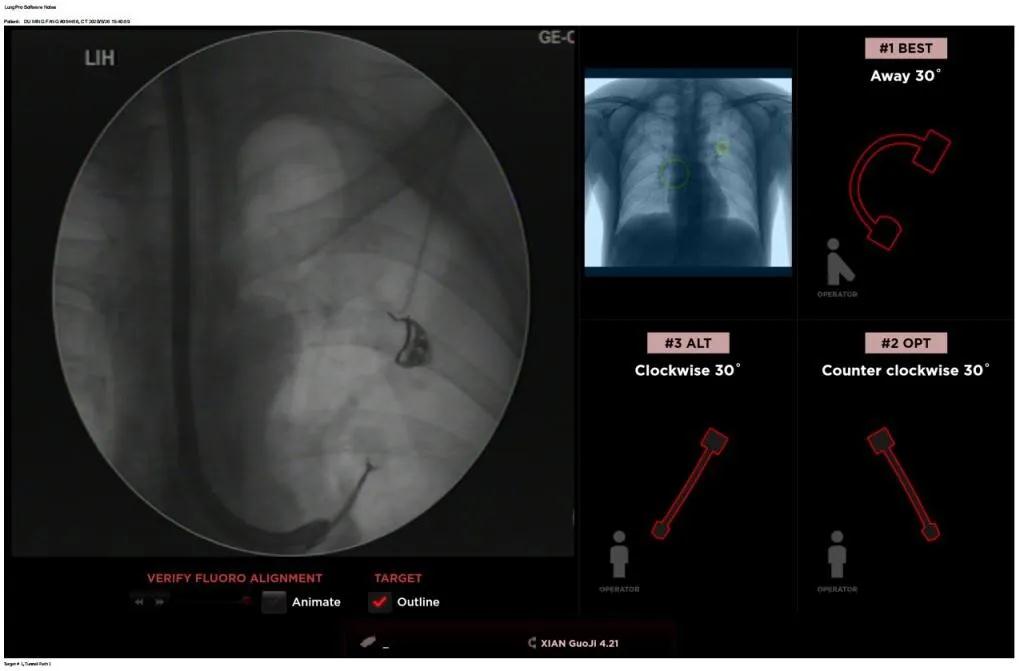

西安國際醫(yī)學(xué)中心醫(yī)院呼吸內(nèi)科完成西北地區(qū)首例LungPro全肺導(dǎo)航系統(tǒng)引導(dǎo)下BTPNA手術(shù)

近日,西安國際醫(yī)學(xué)中心醫(yī)院胸科醫(yī)院歐陽海峰副院長完成西北地區(qū)首例LungPro全肺導(dǎo)航系統(tǒng)引導(dǎo)下經(jīng)支氣管鏡跨肺實(shí)質(zhì)肺外周結(jié)節(jié)活檢術(shù)。

患者是一位59歲的男性,入院診斷左固有上葉前段肺小結(jié)節(jié),大小1.5cm*1.5cm。因?yàn)椴≡钆c支氣管不相通,無法開展經(jīng)支氣管自然腔道的活檢,而且病變距離胸壁較遠(yuǎn)、肋骨阻隔進(jìn)針線路、病灶周圍有血管包繞,如果進(jìn)行CT引導(dǎo)下經(jīng)皮肺穿刺活檢,則存在較大的氣胸、出血等并發(fā)癥的風(fēng)險。

經(jīng)過充分的討論后,歐陽海峰副院長決定為患者實(shí)施LungPro全肺導(dǎo)航系統(tǒng)引導(dǎo)的經(jīng)支氣管跨肺實(shí)質(zhì)肺外周結(jié)節(jié)活檢術(shù)。Broncus導(dǎo)航系統(tǒng)LungPro具有全球領(lǐng)先獨(dú)創(chuàng)的BTPNA技術(shù)(支氣管鏡下跨結(jié)節(jié)抵達(dá)術(shù)),可以實(shí)現(xiàn)對氣道外周孤立性肺小結(jié)節(jié)的精準(zhǔn)定位,建立直接通往氣道外病變部位的通道,以實(shí)現(xiàn)全肺的診斷及后續(xù)治療。這項(xiàng)技術(shù)不僅彌補(bǔ)了現(xiàn)有支氣管鏡技術(shù)由于受限于病變部位是否有氣道可通向以及無法準(zhǔn)確定位病變部位而造成的較低診斷率,同時還彌補(bǔ)了CT引導(dǎo)下經(jīng)胸穿刺(TTNA)無法適用于某些特定部位如中央及肩胛骨等結(jié)節(jié)的問題,并且還避免了經(jīng)胸穿刺給患者帶來氣胸、出血的高風(fēng)險,可有效提高肺部結(jié)節(jié)及早期肺癌診斷陽性率,亦可用于早期肺癌的射頻消融或微波治療,具有微創(chuàng)、安全、同期雙肺診療等優(yōu)勢。

BTPNA技術(shù)整合了虛擬導(dǎo)航支氣管鏡VBN、氣道內(nèi)超聲rEBUS、TBNA、高壓球囊擴(kuò)張、X線輔助等多項(xiàng)三、四級呼吸內(nèi)鏡技術(shù)。歐陽海峰副院長有3000 TBNA、1000 rEBUS、500 VBN、800 球囊擴(kuò)張方面的技術(shù)積累,10年來個人每年完成三、四級呼吸內(nèi)鏡手術(shù)1200余例,這有效保障了BTPNA技術(shù)的順利開展。

團(tuán)隊(duì)術(shù)前進(jìn)行了精心的準(zhǔn)備,通過高分辨率CT建立了導(dǎo)航路徑,在麻醉科手術(shù)室的配合下,借助LungPro引導(dǎo)順利的確定了病灶部位、建立隧道并實(shí)施活檢,術(shù)后患者恢復(fù)順利出院。